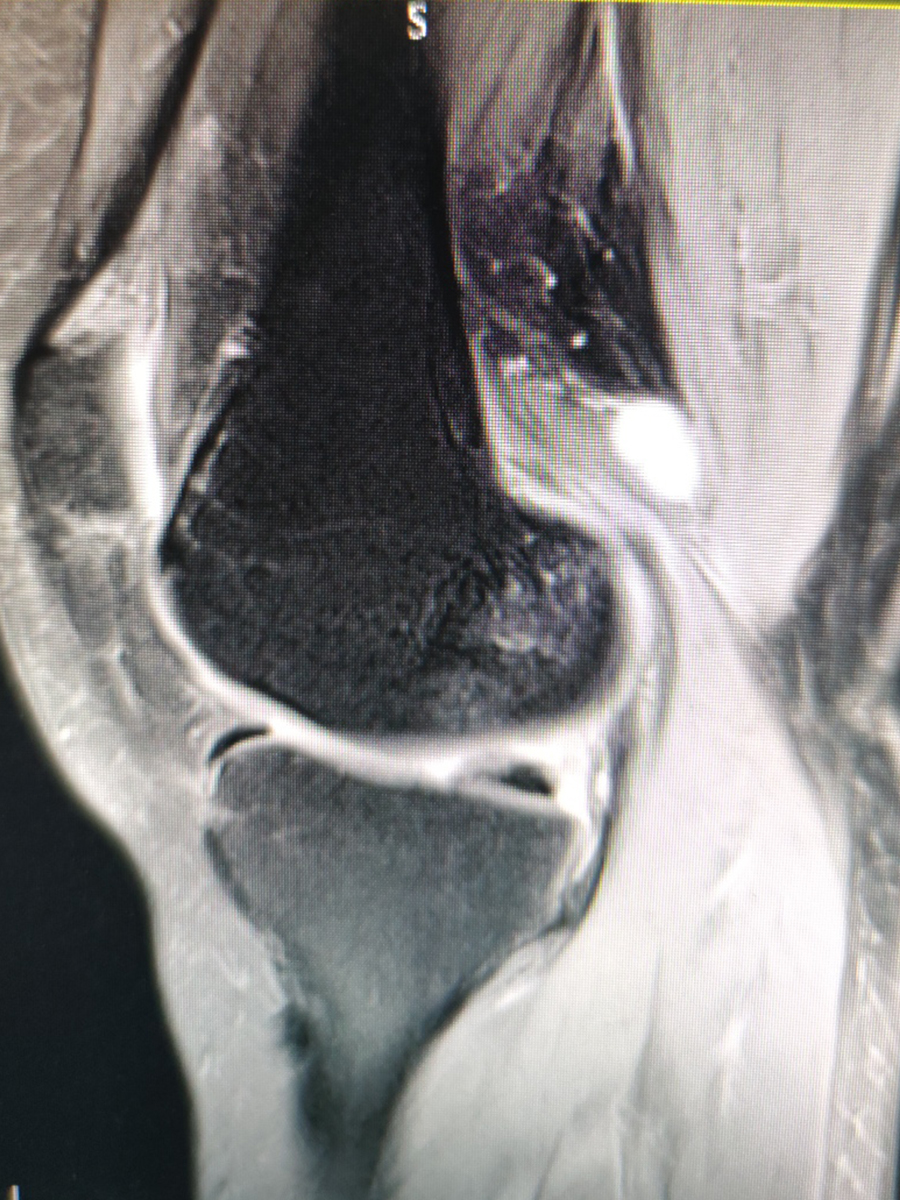

患者是一位中年女性,1个月前出现右膝疼痛,伴乏力,主要是下蹲起身时无力,疼痛以腘窝处为重,劳累后有加重迹象,休息后减轻,无肢体麻木。我给患者进行体格检查,发现右膝内侧压痛、肿胀,膝关节被动活动没有明显受限,承重屈膝60°受限,腘窝处可以触及肿块,大小1×2cm。嘱患者进行磁共振检查,提示关节积液和腘窝囊肿。综合其临床症状以及相关检查结构,以关节病收入我院,进行下一步治疗。